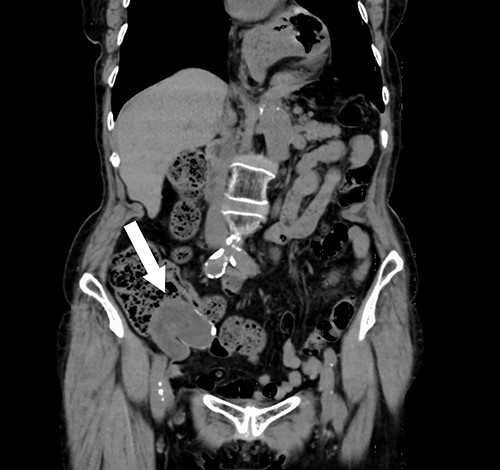

A 74-year-old female with hypertension, hyperlipidemia and hyperuricemia had a colonoscopy as a screening examination. The colonoscopy revealed an extrinsic compression with ulceration located at the cecum (Fig. 1). A multidetector computed tomography (CT) identified a low-attenuation distorted cystic lesion with focal calcification in the anatomic region of the right iliac fossa, measuring 6.1 × 5.0 × 3.7 cm (Fig. 2). Findings from the routine laboratory examinations were unremarkable, and all tumor markers were within normal range. The patient was scheduled for ileocecal resection with lymph node dissection due to the possibility of malignancy, such as appendiceal mucinous adenocarcinoma, because of the large and distorted tumor. Contrast-enhanced CT was conducted for further assessment of the findings, and we found that the cystic lesion was dramatically shrinking. It seemed improbable that rupture of the tumor had happened since no findings implied the spread of mucinous components, such as ascites or mucinous peritoneal nodules on CT. It was considered that the mucinous content was spontaneously drained from the root of the appendix to the cecum. However, the enhanced and distorted lesion with focal calcification, suggesting malignancy, had remained in concordance with the base of appendix (2.7 × 2.1 × 1.9 cm) (Fig. 3). Therefore, ileocecal resection was performed as planned, and laparoscopic procedure was selected due to the unlikelihood of the tumor rupturing. The base of appendix was distended and there were no obvious peritoneal anomalies upon visualization of the abdomen (Fig. 4). The specimen was handled with care and there was no spillage of cystic contents. The post-operative course was uneventful, and the patient was discharged on post-operative day 8.

Contrast-enhanced CT showing the enhanced and distorted lesion with focal calcification (arrow).